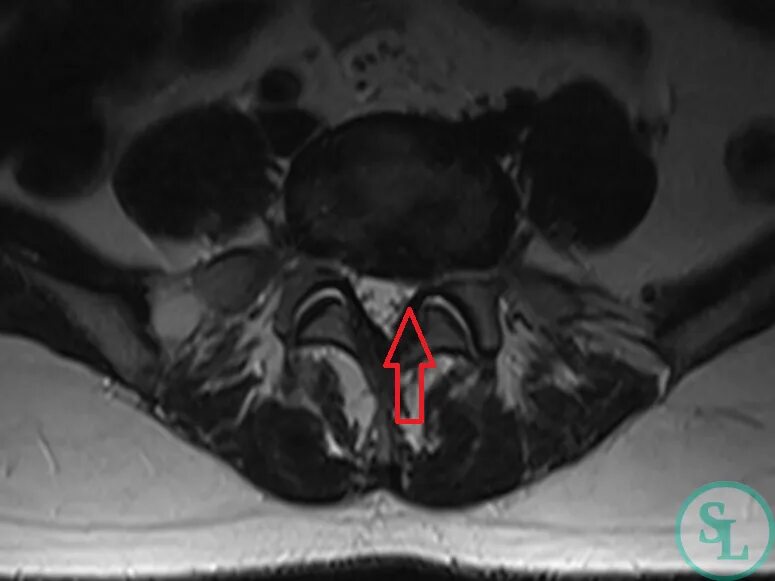

Грыжа экструзия диска l5 s1